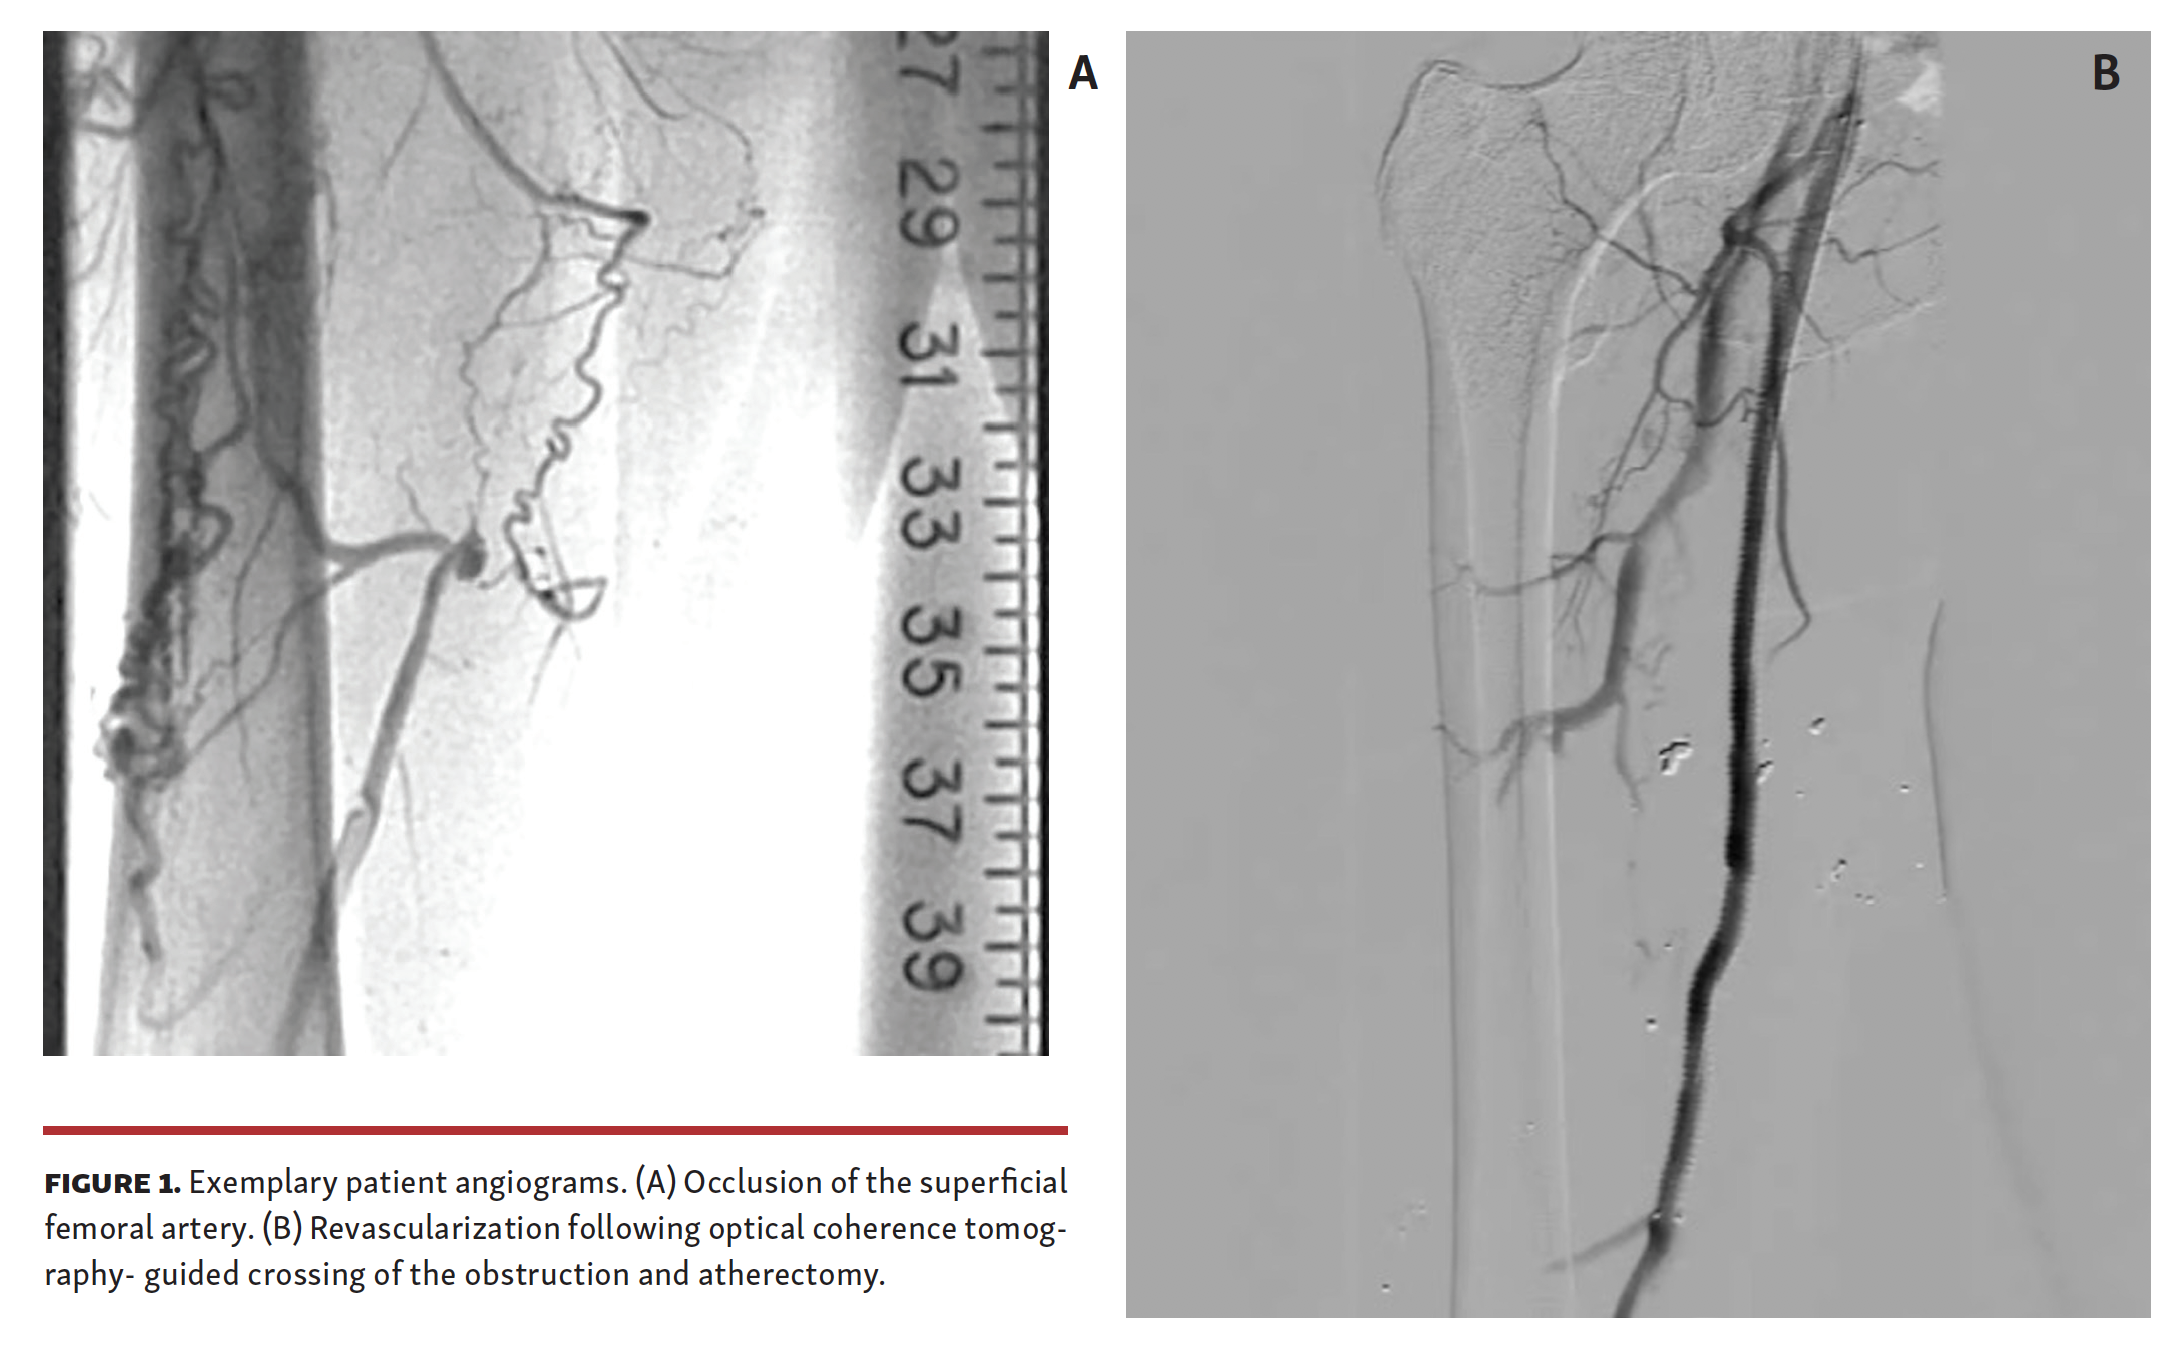

The pilot phase of the HIPACT study was a prospective assessment of histologic samples obtained from patients who underwent atherectomy of obstructive lesions in FP arteries. Patients were eligible for the study if they had chronic PAD (Rutherford-Becker categories 2–5) and occlusions within a FP segment (Figure 1). Patients were ineligible if they were taking oral anticoagulants, had a history of contrast allergy, or had undergone attempted treatment or atherectomy of the target CTO previously. Patients returned to the clinic within 6 months after the procedure for symptom assessment, ankle-brachial index evaluation, and documentation of any repeat procedures since treatment.

The patients were prepared for surgery following standard procedures. The target lesion was identified by angiography and its length was documented. With the lesion identified, the occlusion was traversed with an Ocelot crossing catheter (Avinger) (Figure 2) and then subsequently treated with TurboHawk directional atherectomy (Medtronic). Excised tissue was captured in the nosecone of the atherectomy device and collected at the end of the procedure, fixed in 10% neutral buffered formalin following standard methodology, and sent to the pathology lab.

A total of 19 patients participated in this pilot phase of the HIPACT study; they were predominantly male (67%) with a mean age of 72 ± 11.6 years. The CTO lesions were primarily (67%) in the superficial femoral artery (SFA), with 4 in a popliteal artery, and 1 each in the tibial peroneal trunk and the common iliac artery. All obstructions were crossed successfully by the crossing catheter with no dissections or perforations. Directional atherectomy reduced the obstructions such that blood flow was restored through the area of the obstruction, as determined by angiography. The amount of fluoroscopy time varied with the device used, with less than a minute of time (14 seconds) needed when the OCT-guided catheter was advanced through the obstruction to prepare a path for the atherectomy device (Figure 3).